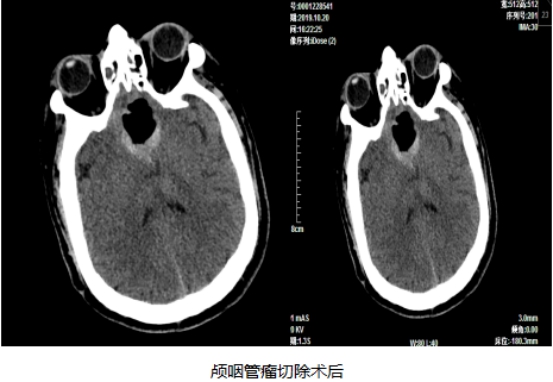

颅咽管瘤切除术前

10月20日上午8:30,手术准时开始,从麻醉、铺巾、消毒、内镜器械准备,再到术中切除,一切都井然有序的按照北京天坛医院的手术流程进行着,经桂松柏教授、刘春辉教授以及市第一人民医院神经外科主治医师朴金伟的不懈努力,顺利于上午11:20全切肿瘤。术后患者恢复良好,目前患者已经能够下床行走,近日即将出院。